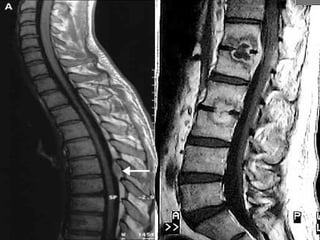

Magnetic resonance imaging

lumbosacral spine showing a

T1W isointense lesion

intradural extramedullary

lesion at D12-L1 level

measuring about 11.4 × 11.2

× 22.8 mm displacing the

conus and cauda (a and b).

On contrast (c and d) there is

heterogenous enhancement

with hypointense center and

peripheral enhancement